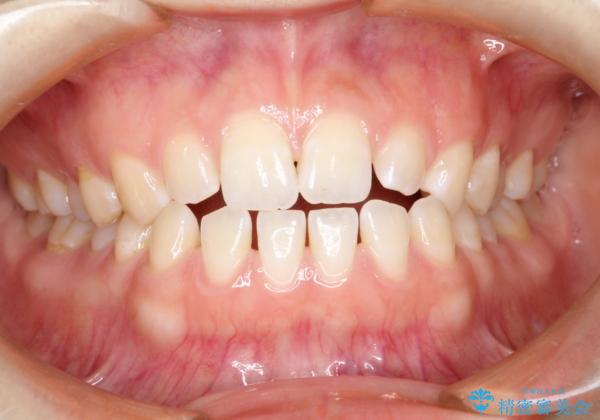

前歯の隙間を閉じたい インビザラインによる矯正

- 上下の前歯に隙間があるとのことで来院されました。

インビザラインにて隙間を閉じる矯正を行いました。